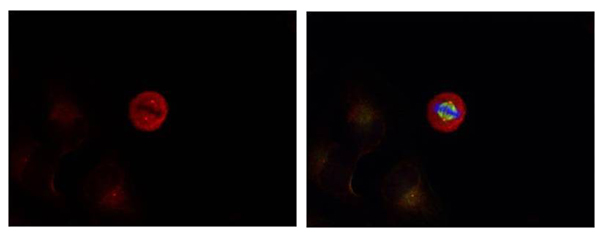

Immunofluorescence staining of methanol-fixed Hela cells showing centrosome and nuclear staining using p44/42 MAP Kinase (Phospho-Tyr204) Antibody #11246.